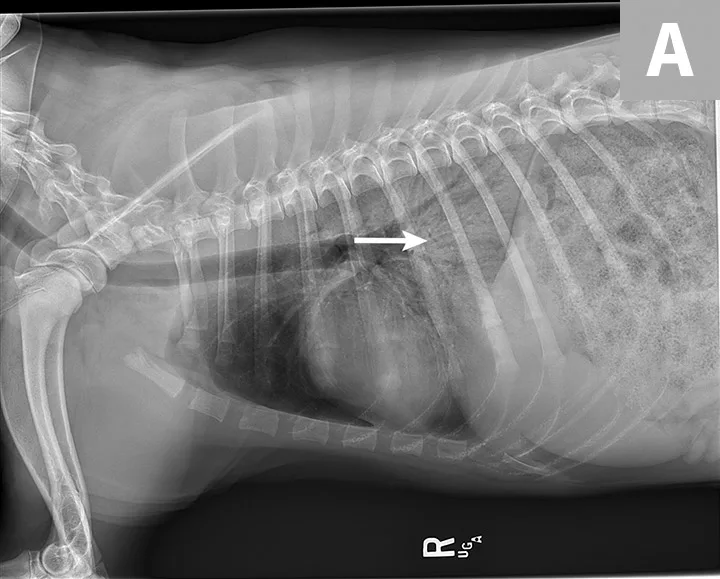

Blood pressure was decreased (85 mm Hg) on Doppler ultrasound. Oxygen saturation was initially 92% but increased to 98% with flow-by oxygen supplementation via mask (4 L/minute). Initial blood work showed mild hyperlactatemia (3.1 mmol/L; reference range, 0-2.5 mmol/L), packed cell volume of 54%, and total solids at 6.8 g/dL. Chest radiography was performed with oxygen supplementation and revealed a moderate to severe caudodorsal interstitial to alveolar lung pattern (Figures 1 and 2).

Radiographs showing caudodorsal alveolar pattern consistent with noncardiogenic pulmonary edema (arrows). Edema is caudodorsal and bilateral. The heart size is normal, and there is no elevation of the airways that would indicate left-sided heart enlargement. Sternal contact of the heart, which might suggest right-sided heart enlargement, is minimal.

The caudodorsal, bilateral, interstitial to alveolar pattern seen on radiographs is most consistent with noncardiogenic pulmonary edema (NCPE). Other differential diagnoses typically include cardiogenic edema or pneumonia. However, because Charlie was 6 months of age with a normal heart size and no murmurs or arrhythmias auscultated, cardiogenic edema was less likely. Expected pulmonary changes to the lungs are more diffuse with fungal or viral pneumonia or more discrete with bacterial pneumonia. NCPE was most likely in this patient because of the caudodorsal, bilaterally symmetric pattern and history of presumptive electrocution.